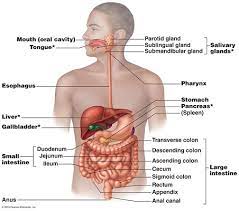

قیمت: 49٬000 تومان - دسته بندی فایل: پاورپوینتمروری بر آناتومی و فیزیولوژی دستگاه گوارش (ppt) 38 اسلاید

فروش ویژه پاورپوینت حرفه ای مروری بر آناتومی و فیزیولوژی دستگاه گوارش / تعداد اسلاید: 38 اسلاید